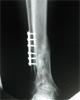

Post

Op

Stabilised using ligamentotaxis,fibular fixation and ring fixator application